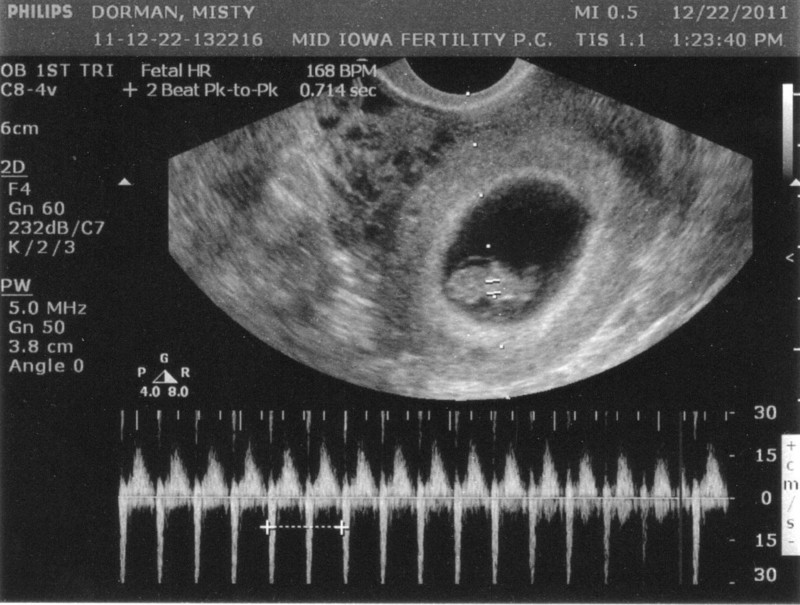

Ở tuần thứ 8 của thai kỳ, sự phát triển của thai nhi diễn ra nhanh chóng. Thai nhi đã bắt đầu chuyển động nhẹ, nhịp tim cao gấp đôi so với mẹ và các cơ quan trong cơ thể đang phát triển mạnh mẽ. Lúc này mẹ sẽ phải bất ngờ với hình ảnh khi siêu âm thai 8 tuần tuổi.

Siêu âm thai 8 tuần là bước quan trọng đầu tiên mà các mẹ bầu thực hiện sau khi biết tin mang thai. Trong giai đoạn này, thai nhi đã bắt đầu phát triển và siêu âm thai cung cấp một cái nhìn tổng quan về tình trạng của thai nhi cũng như xác định độ tuổi chính xác. Thai nhi phát triển khá nhanh sau 8 tuần và thông qua siêu âm, mẹ bầu có thể nắm bắt được các chỉ số chiều dài đầu mông và đường kính túi thai. Trung bình với sự phát triển ổn định, kích thước của thai nhi có thể đạt khoảng 15mm với đường kính túi thai khoảng 30mm. Điều này cung cấp thông tin quan trọng giúp mẹ bầu và bác sĩ theo dõi sự phát triển của thai nhi.

Đến tuần thai thứ 8, phần đuôi thai của thai nhi đã hoàn toàn biến mất và thay vào đó là sự hình thành của các cơ quan quan trọng như tay, chân, mắt, mũi, miệng và tim thai. Tuy nhiên, do kích thước của thai nhi vẫn còn rất nhỏ, nên mẹ bầu chưa thể nhìn thấy rõ bé khi thực hiện siêu âm ở tuần thứ 8.

Thông thường thai nhi ở tuần 8 đã phát triển tim thai với 4 ngăn, vách tim và bắt đầu đập những nhịp đầu tiên. Nhịp tim của thai nhi trong giai đoạn này thường dao động từ 100 - 160 nhịp/phút. Tuy nhiên, một số trường hợp khi mẹ bầu thực hiện siêu âm ở tuần 8 có thể không thấy tim thai. Điều này có thể là do: